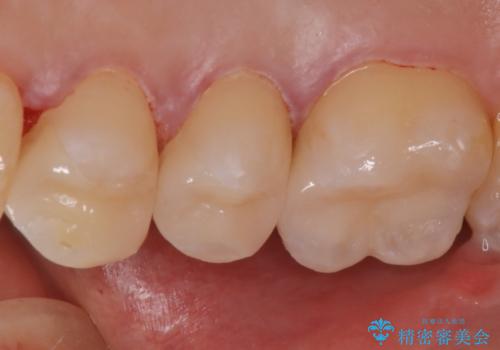

セラミックインレーのセット後は、食べ物がはさまることがなくなり、経過も良好で口腔内の環境もいい状態を保てています。